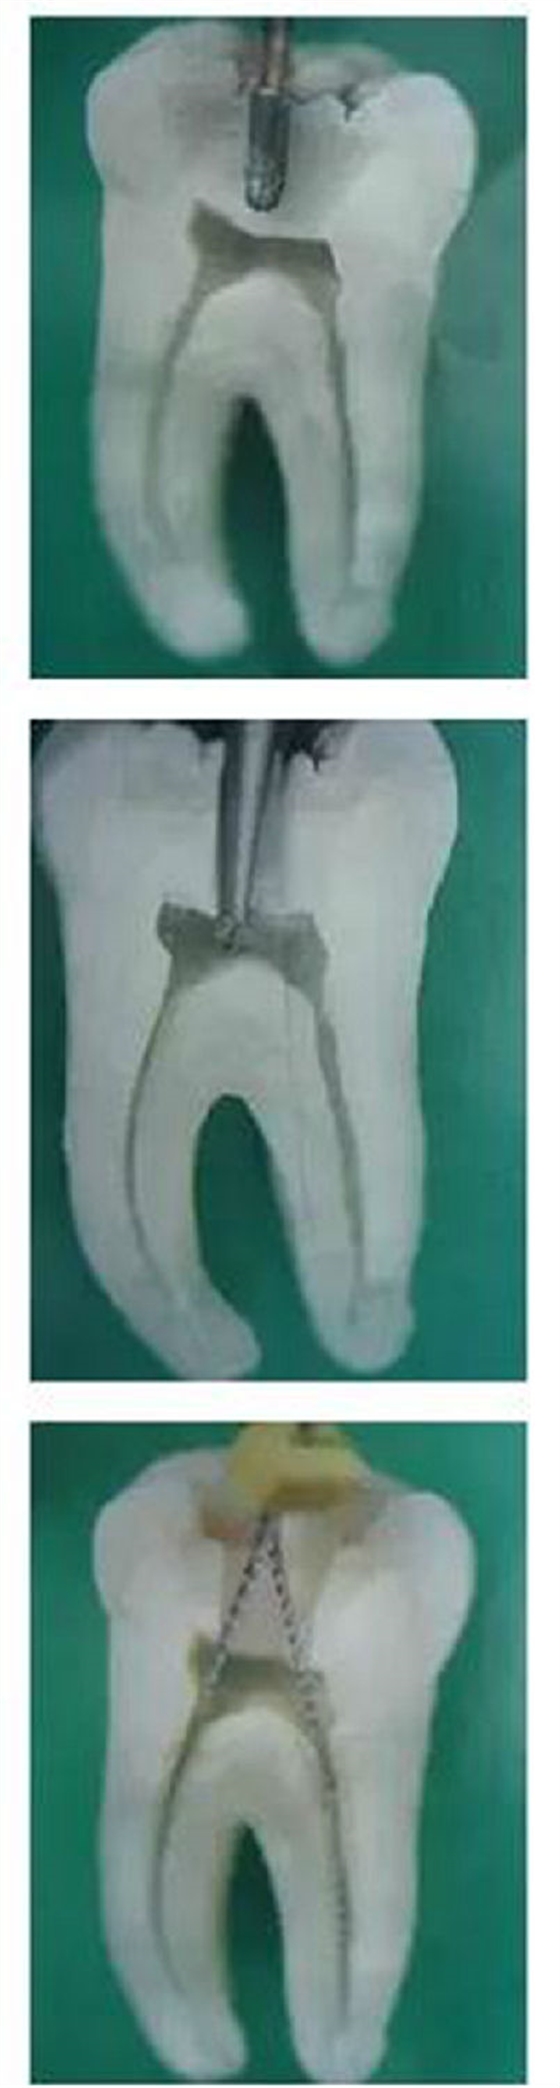

圖1,裂鉆鉆到近髓 2,球鉆穿髓 3,小號銼探查根管口

圖4,球鉆揭髓頂 5,修整洞型 6,完成開髓

1,彎曲根管冠部處理之前;2,用GG鉆或SX銼進行預(yù)備;3,處理后形成的直線通道

我的病例1_____冠部處理成直線通道后的充填效果

我的病例2_____下頜7"C"型根管的充填效果